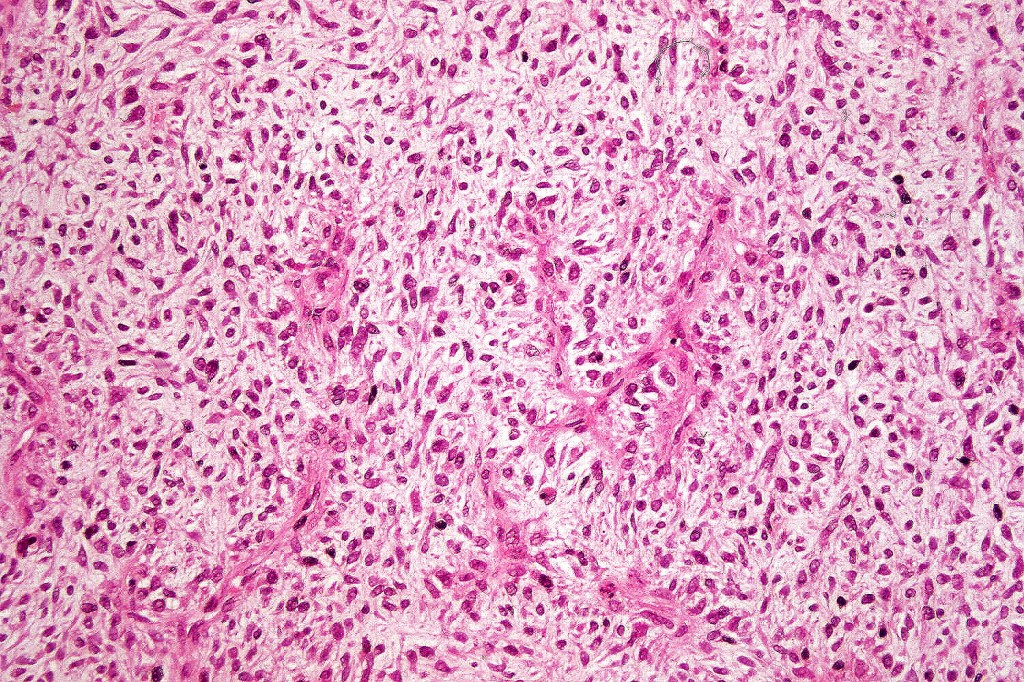

Carcinosarcoma

Cutaneous carcinosarcoma (metaplastic carcinoma, carcinoma with heterologous differentiation)

Histological features

•Smooth muscle